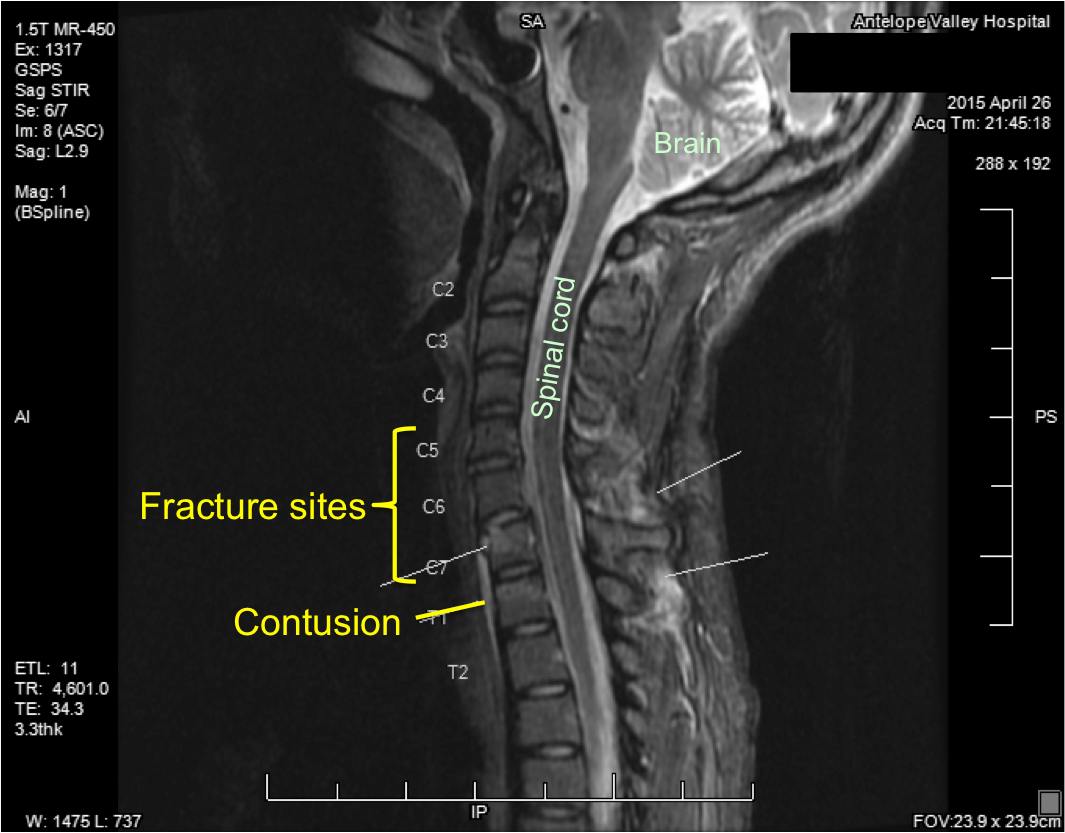

My neck injury Keeping my head up high Can Ms Be Seen On Neck Mri Ms lesions can appear in both the brain’s white and gray. In ms your immune system attacks the myelin coating surrounding nerves. Mri scans can pick up these areas of damage, called. The number of lesions on an initial mri of the brain (or spinal cord) can help assess your risk of developing a second attack in the future and.. Can Ms Be Seen On Neck Mri.